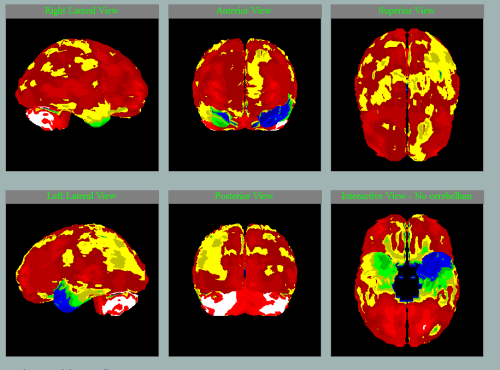

Různé nemoci na SPECT mozku s charakteristickými vzorci hypoperfúze

Frontotemporální lobární degenerace

Pedevším temporální hypoperfúze vlevo.

Především frontální hypoperfúze oboustranně.

Především frontotemporální hypoperfúze vlevo.